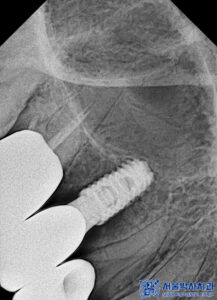

임플란트 식립 전에는 CT 촬영을 통해

뼈의 두께와 높이,

신경과의 거리 등을

정밀하게 확인했습니다.

CT 결과를 바탕으로 식립 각도와

깊이를 세밀하게 계획하고,

충분한 뼈 지지가 확보될 수 있도록

맞춤형 임플란트 계획을 수립하였습니다.

먼저 왼쪽 위 치아 부위의

기존 보철물을 제거한 뒤

임플란트 식립을 진행했습니다.

치아가 오랫동안 없는 상태로 유지되다 보니

잇몸뼈가 일부 흡수되어

양이 부족한 상황이었습니다.

이에 따라 부족한 뼈를 보강하기 위해

뼈이식을 함께 진행하며

임플란트를 식립했습니다.